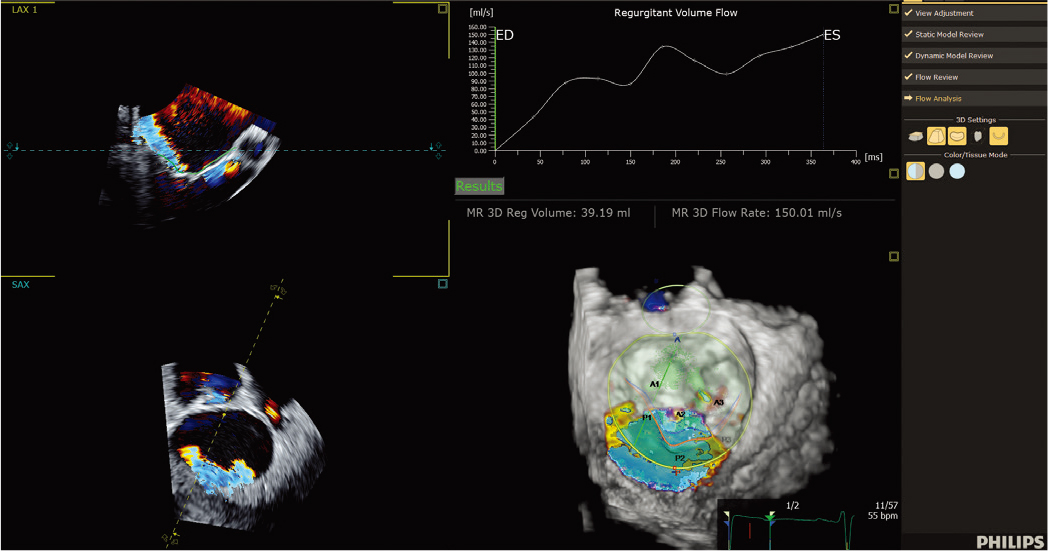

![]() 3D 自动彩色血流定量* 提供 AI 来快速、简单且可重复地测量二尖瓣反流 (MR) 体积,以帮助评估 MR 严重程度。 | ![]() 3D 自动三尖瓣定量* 人工智能通过精确的术中TV环测量(初始尺寸确定和CT计划)帮助确认/重新评估设备尺寸/选择。 |

X5-1c 探头彩色多普勒二尖瓣返流(MR) |